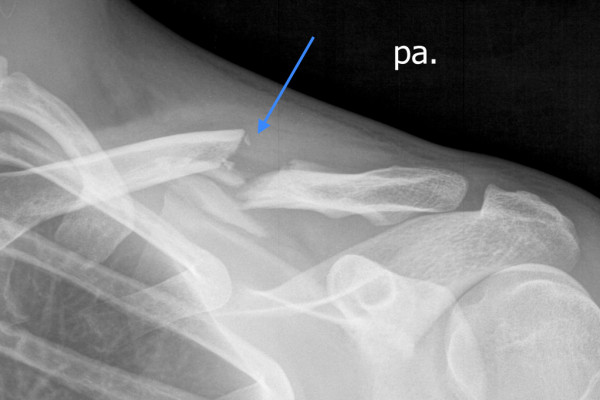

Verschobener Bruch des Schlüsselbeins

Abb. 1: Verschobener Bruch des Schlüsselbeins (Pfeil zeigt auf den Bruchspalt)